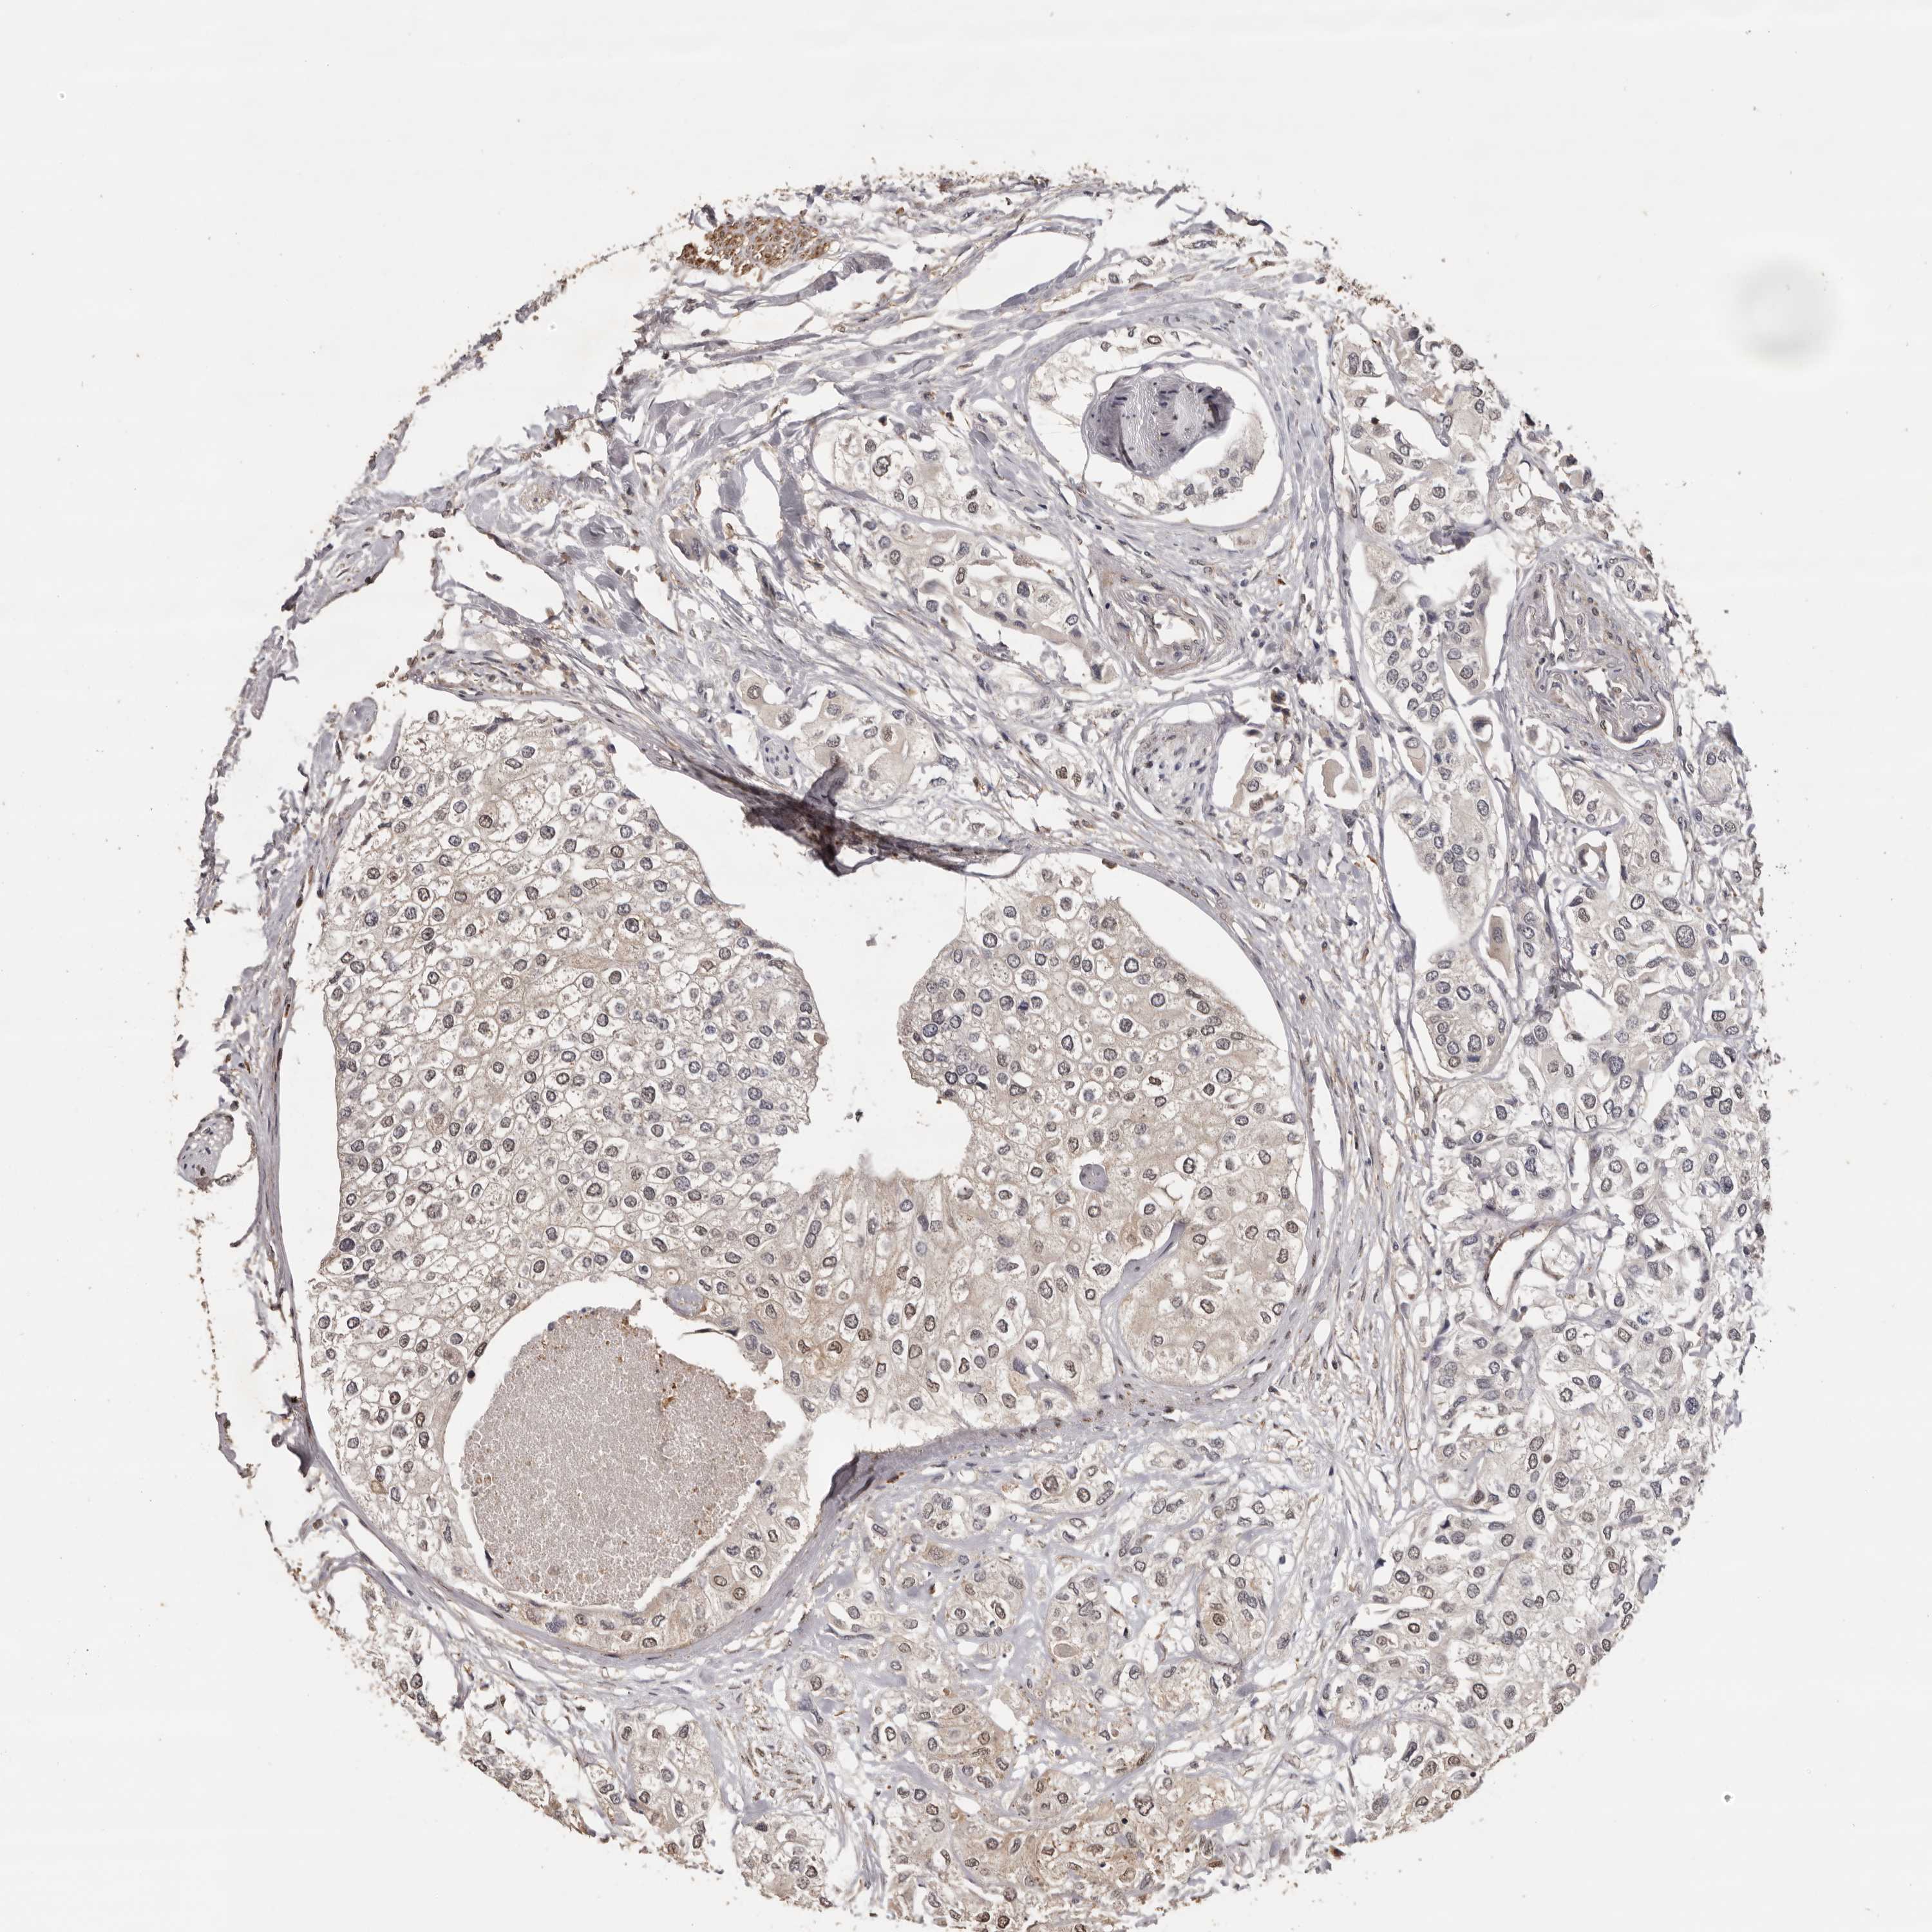

UROTHELIAL CANCER - Protein expressioni

A mouse-over function shows sample information and annotation data. Click on an image to view it in a full screen mode. Samples can be filtered based on level of antibody staining by selecting one or several of the following categories: high, medium, low and not detected. The assay and annotation is described here.

Note that samples used for immunohistochemistry by the Human Protein Atlas do not correspond to samples in the TCGA dataset.

Antibody stainingi

Antibody staining in the annotated cell types in the current human tissue is reported as not detected, low, medium, or high, based on conventional immunohistochemistry profiling in selected tissues. This score is based on the combination of the staining intensity and fraction of stained cells.

Each image is clickable and will lead to virtual microscopy that enables deeper exploration of all samples and also displays staining intensity scores, fraction scores and subcellular localization as well as patient and tissue information for each sample.

Antibody HPA023081

Antibody HPA023103

Antibody HPA024795

Staining

High

Medium

Low

Not detected

Intensity

Strong

Moderate

Weak

Negative

Quantity

>75%

75%-25%

<25%

None

Location

Nuclear

Cytoplasmic/membranous

Cytoplasmic/membranous,nuclear

Urothelial carcinoma, Low grade

Urothelial carcinoma, High grade